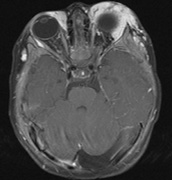

Fig. 7. Neurofibromatosis type 2: Images of a 12-year-old boy with deafness and weakness in his arms and legs, whose father has bilateral deafness. Axial T2-weighted (a) and postcontrast axial (b) T2-weighted images reveal bilateral vestibular schwannomas, which are also known as acoustic neuromas (arrows). This is the classic finding of NF2. (b, c) Bilateral schwannomas are seen in Meckel's cave (arrowheads) and a (d) lower left cranial nerve schwannoma extends into the pars nervosa of the jugular foramen (arrow). (e) A part cystic and part solid enhancing ependymoma in seen within the cervical cord and medulla and within the distal cord and conus. (e, f) Thoracic schwannomas are present at numerous levels (arrowheads). Marked enhancement and thickening of the roots within the cauda equina also represent multiple schwannomas.